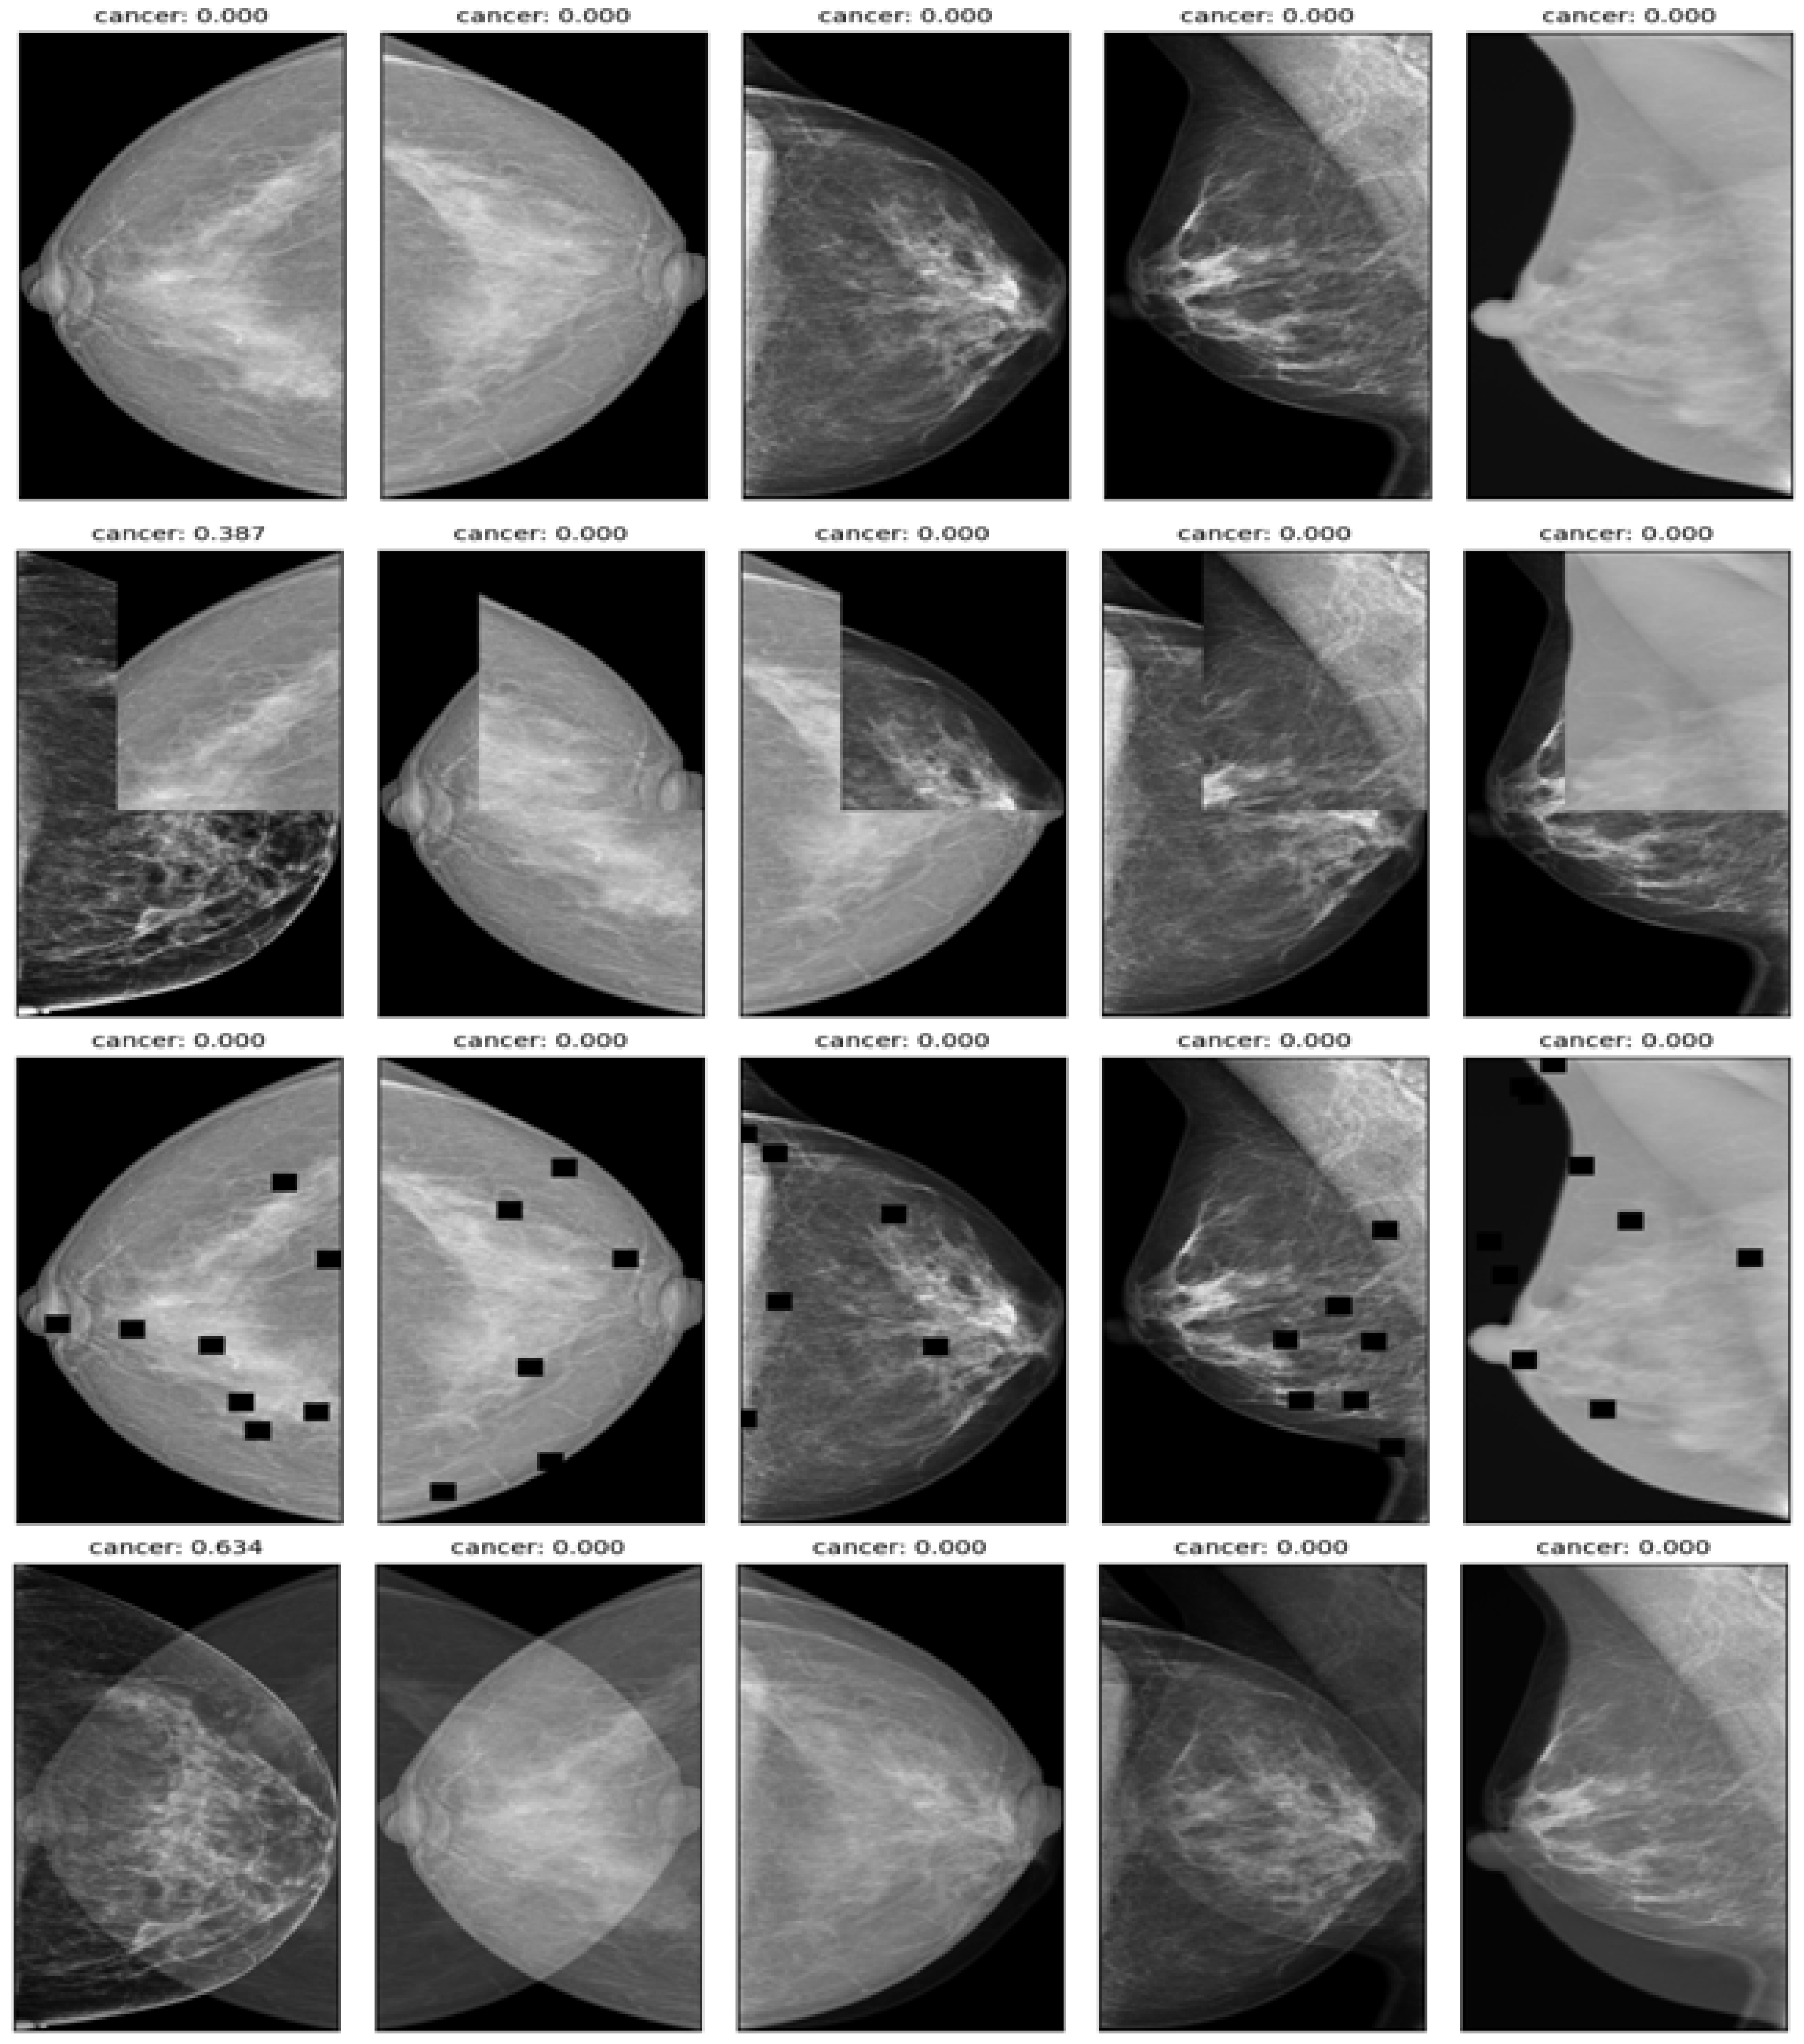

2.3. Preprocessing Image Data

- Mix up: A technique that generates new training samples by linearly interpolating between two images and their labels. This technique can produce high-quality inter-class examples that prevent the model from memorizing the training distribution and improve its generalization ability.

- Cut-mix: A technique that generates new training samples by randomly cutting out patches from two images, pasting them together, and assigning the labels according to the area ratio of the patches. This technique can also produce interclass examples that enhance the model’s robustness to occlusion and localization errors.

- Drop-out: A technique randomly drops out units in a neural network layer during training to prevent overfitting. This technique can decrease the co-adaptation of features and increase the diversity of feature representations.

- Affine transform: A technique that applies geometric transformations such as scaling, rotation, translation, and shearing to the images. This technique can increase the invariance of the model to geometric variations and improve its performance on unseen images.